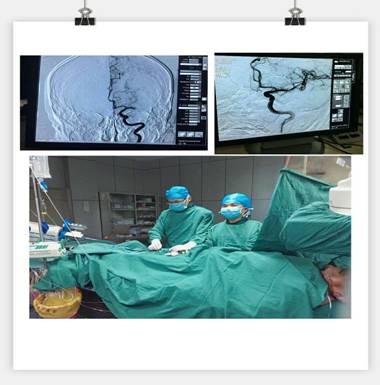

凌晨3點(diǎn)30分, “叮叮?!币魂嚰贝俚碾娫掜戔彺蚱屏松钜沟膶?kù)o。 “你好,這里是急診科,請(qǐng)準(zhǔn)備一張男床,腦血管意外患者”。患者是一名63歲男性,突發(fā)右側(cè)肢體乏力5.5小時(shí),由家屬用輪椅推送入院。入科后患者神志昏睡,心率48次/分,血壓186/100mmHg,NIHSS評(píng)分20分。病人情況十分危急,在劉禮泉主任指示下,患者為急性缺血性卒中,有溶栓指征。在劉主任與家屬談話期間,值班醫(yī)生同時(shí)開出醫(yī)囑,患者予以硝普鈉控制血壓+尿激酶靜脈溶栓。夜班護(hù)士立即給病人抽血、吸氧、心電監(jiān)護(hù)、建立靜脈通道、準(zhǔn)備藥物……我們忙而不亂,默契配合。溶栓過程中劉主任一直守護(hù)在病人身旁,隨時(shí)觀察病人的病情變化。溶栓后,患者右側(cè)肢體有自主活動(dòng),但乏力癥狀及意識(shí)障礙無(wú)明顯緩解,劉主任立即決定行頭頸聯(lián)合CTA,明確是否有大血管閉塞。果不其然,患者頭部CTA提示左側(cè)大腦中動(dòng)脈M1段栓塞,如果大血管得不到及時(shí)開通,必然會(huì)出現(xiàn)災(zāi)難性的后果。劉主任建議家屬考慮是否行血管內(nèi)治療開通血管,經(jīng)過耐心細(xì)致的溝通,患者家屬同意行急診腦血管造影檢查及血管內(nèi)治療。 同時(shí)立即召集曾比賢副主任、聶利珞副主任趕來(lái)醫(yī)院,為患者在局麻下行全腦血管造影+顱內(nèi)血管取栓術(shù)。時(shí)間伴隨著沉悶緊張的氣氛一分一秒地過去,取栓的生命通道終于打開,患者病變血管恢復(fù)良好,手術(shù)圓滿成功,此時(shí)灰暗的天才微微光亮……

在急性腦梗死患者緊急救治中,時(shí)間就是生命,該病例運(yùn)用了動(dòng)靜脈聯(lián)合的方式治療急性腦梗塞,有效地保護(hù)了患者的大腦,此類技術(shù)在國(guó)內(nèi)處于領(lǐng)先治療手段,溶栓、取栓同步進(jìn)行的橋接搶救措施起到了至關(guān)重要的作用。該病例成功取栓意味著我院神經(jīng)內(nèi)科在治療急性腦血管病方面已經(jīng)從傳統(tǒng)的靜脈溶栓向介入取栓的現(xiàn)代化治療方式轉(zhuǎn)變。